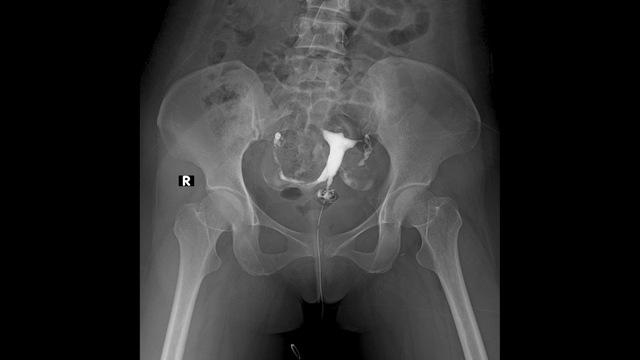

X quang